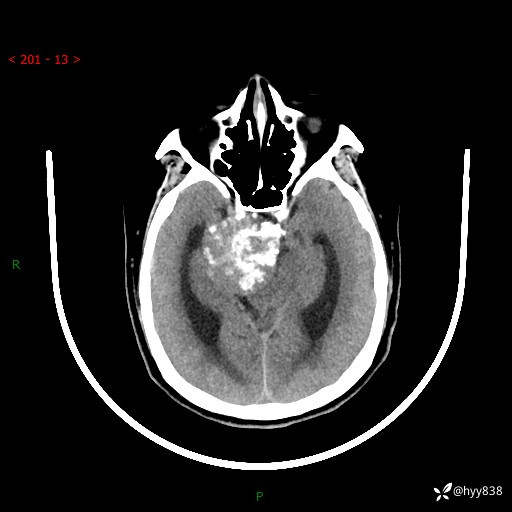

52岁/女,发现颅内占位4天。颅底钙化性肿块---结果公布~

颅脑CT平扫